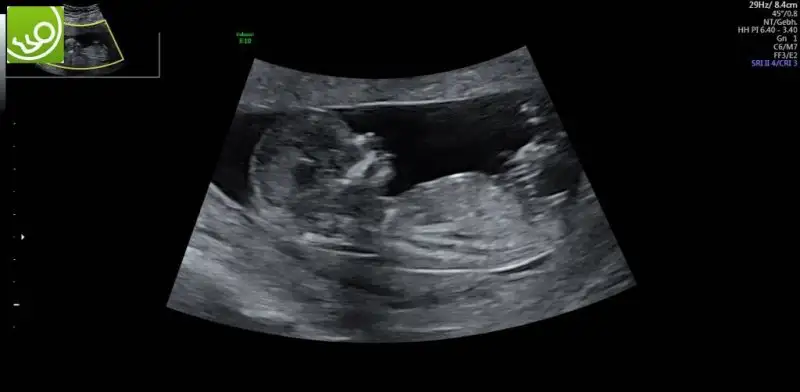

kizlar iki gunden beri icimi kemiren bisi var sizlerle paylasmak istiyorum yardimci olursaniz sevinirim ikili test yaptirdik bildiginiz uzere dr hersey normal dedi ve kan testi icin hafta ya gun verdi test kagidinda birtek mide cebi gorulmemistir yaziyordu dr haftaya gelince tekrar bakariz dedi hersey normal dedu ama benim icim icimi yiyor ne olur dua edin ve yardimci olun boyle bisi duyan varsa bilgi paylasabilir mi

Bazı organlar 13.haftada daha rahat görünüyor canım, o yüzdendir. Bizde iki hafta sonra yine gideceğiz ki kalpteki 4 odacığı görmek için. Rahat olmaya çalışalım olur mu?

Bazen bebegin pozisyonundan dolayi tam istedikleri gibi net goremeyebiliyorlar. Onun icin tekrar bakilacak demis olabilir.Net gormeden rapora yazmak istememis olabilir.